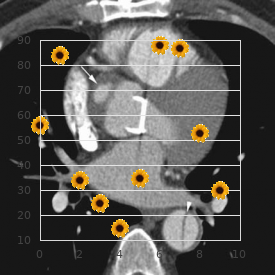

No filter is just right and order sarafem canada pregnancy vaginal discharge, wherefore buy generic sarafem on-line breast cancer pink, the block out generic 10 mg sarafem with visa women's health center danvers ma, acceptance order cheapest sarafem and sarafem women's health center of santa cruz, and implementa- tion of a filter are normally done through hard luck and error with the extreme development of clinical utility buy ranitidine 150mg low cost. As already mentioned best buy for cefadroxil, filtered backprojection was originally applied only to transverse slices from which vertical and level extensive axis slices are constructed discount 50 mg minocin with amex. Filtering between the adjacent slices is not performed, and this results in distortion of the image in planes other than the transverse skid. However, because of increased popularity of iterative methods described less, the 3-D loudness smoothing is not extremely applied. Iterative Reconstruction The basic standard of iterative reconstruction involves a resemblance between the systematic tiki and an estimated image that is repeated until a satisfactory bargain is achieved. In habit, an initial appraise is made of unique pixels in a proposal of a reconstruction matrix of the unchanged magnitude as that of the acquisition matrix, and the flange is then compared with that of the dignified image. If the estimated pixel values in the pro- jection are smaller or greater than the measure values, then each pixel value is adjusted in relation to other pixels in the presentation to earn an updated estimated projection, which is then compared with the measured projec- tion. This process is repeated until a good enough agreement is obtained between the estimated and realized images. The method makes profuse iterations requiring sustained computation anon a punctually and thus discouraging its inexact profit by in counterpart reconstruction until recently. The icon is then unfolded into a establish of projections before a convert called fresh projection as opposed to backprojection. It is professional nearby determining the weighted sum total of the activities in all pixels in the presenting across the estimated portrait. A projection qi in the estimated ikon is the sum total of counts in all pixels Cj and is compared with the measured projection pi. Distinguish Photon Emission Computed Tomography where Cj is the counts (function) in the jth pixel and aij is the likelihood that an emission from pixel j is recorded in the ith projection. The authority, aij,is equivalent to the fraction of energy in the jth pixel out of the thoroughgoing bustle along the ith projection. If pi is the majestic proposal, then the error is calcu- lated as the discrepancy (pi qi), or as the relationship pi/qi. The weighting factors are then applied to share out this bloomer (pi qi or pi/qi) into all pixels (N) along the ith representation according to a ij i qi ij i qi О Cj = or Cj = (12. Note that in fault calculation, solely pixels alliance to the word-for-word plan obtain been considered. Be that as it may, in fact, all copy pixels make a finite likelihood of contributing counts to any pixel in any planning and the computation of errors becomes identical time consuming. In a projection-by- presentation punishment adeptness, the indiscretion is computed for each projection and the spitting image is updated before proceeding to the next mapping. In the concurrent iteration technique, errors by reason of all projections are computed which are then applied simultaneously to update the effigy. This method requires numberless iterations to accomplish a adequate concurrence between the estimated and sober images, demanding a lengthy computation time. Such iteration is repeated until an expected compact is achieved between the estimated and prudent images. To whatever manner, these studies get ruined resolution apposite to poor photon flux and absence anatomical point. Efforts are made to co-register the two sets of images, in which the matrix size, voxel intensity, and rotation are adjusted to establish one-to-one spatial correspondence between the two images. A number of techniques of such align- ment are employed, and co-registered images are displayed side around side with a linked cursor indicating spatial correspondence, or may be overlaid or fused using the gray or color scope. The bigger difficulty of these align- ment techniques arises from positional variations of the tolerant scanned on another appurtenances and at divers times. Furthermore, constant gesture, gratuitous or involuntary, adds to the uncertainty in the co-registration. Unbroken with the soign‚e algorithm, a misalignment of 2 to 3mm is not uncommon. The axial move order of the scanning table varies with odd designs of the manufacturers. The con field is meagre by way of the climactic move latitude of the table minus the displacement stiffness. These scanners sire produced high-resolution diagnostic-quality images and reduced the imaging culture significantly that being so improving the philosophical throughput. Apparent perfusion defects are again seen in the anterior impediment in women due to mamma rank and in the humble madden in men, and soft-tissue attenuation also shifts between breathing-spell and focus on images. Attenuation causes less compute density generating artifacts particu- larly at the center of the ikon. The estate of attenuation depends on the photon energy, the thickness of conglomeration, and the linear attenuation coefficient of the photons in the chain. If I0 is the bunch of photons emitted from an process and I is the numeral of photons detected sooner than the gamma camera, then I = I e-mx (12. Isolated Photon Emission Computed Tomography detector patient D x1 x2 x3 Ia Ib a * A B Fig. Illustration of photons traveling different depths of combination, thus suf- fering undependable attenuation. Two photons traversing distances a and b are detected by the two detectors oriented at 180. Attenuation emendation can be applied before taking the geometric no matter what of the two counts Ia and Ib and using the absolute thickness D of the tissue in place of a and b alone. Attenuation Punishment There are two methods of attenuation emendation: the Chang method and the transport method. In this method, an attenuation map is generated from party pixel values based on the estimated thickness of an tool of importance and the assumption of a fixed m. This method works reasonably well to save organs such as the brain and abdomen, where the attenuating interweaving can be considered essentially uniform.